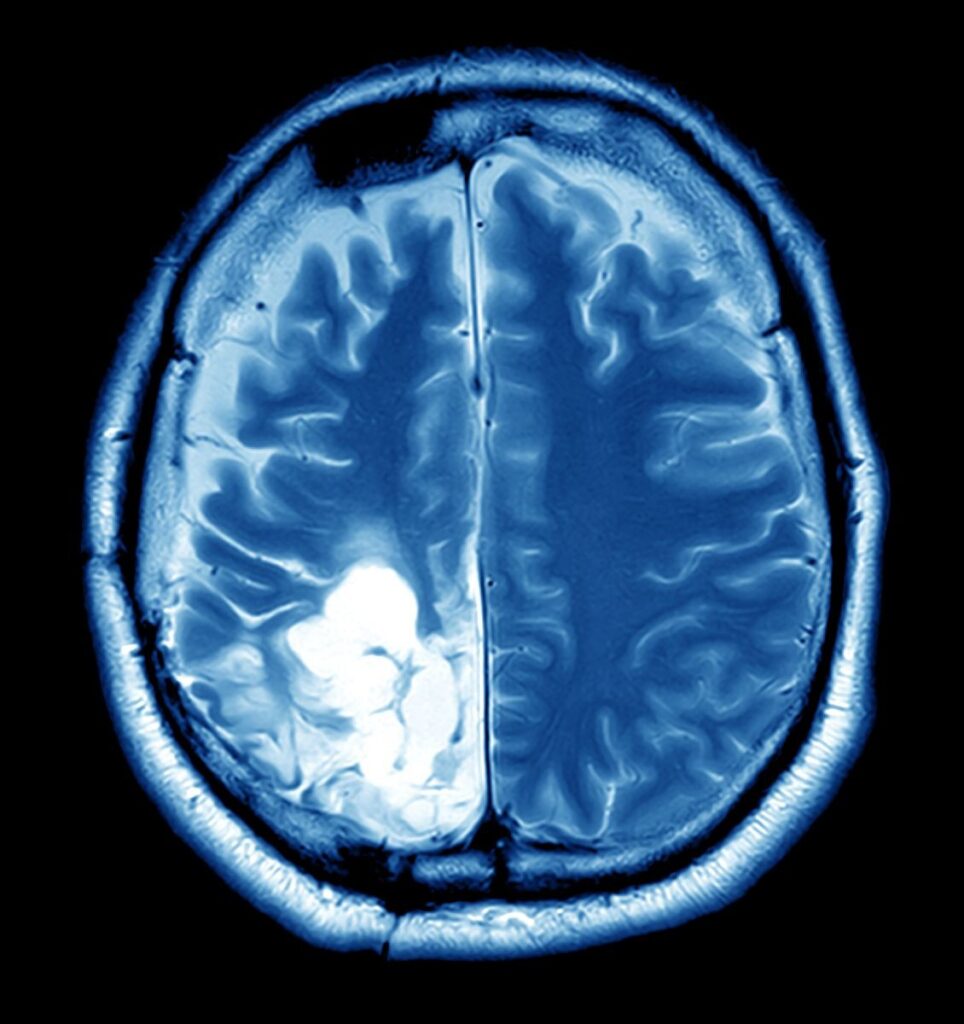

Researchers say that most cases of brain cancer did not had a clear cause, but exposure to a family history and radiation of brain tumors might increase the risk. Typically, brain cancer happened when tumors progress inside the brain or close it. Although brain cancer might originated in the brain, it’s also possible for cancer to spread to the brain from other zones of the body. Researchers agreed that cancerous tumors normally developed after the cell DNA is altered, but, unfortunately, Experts were still trying to figure out what lifestyle factors may contributed to brain cancer. If you were worried about cancer, live the healthy lifestyle and getting wellness exams might support you protect the health.